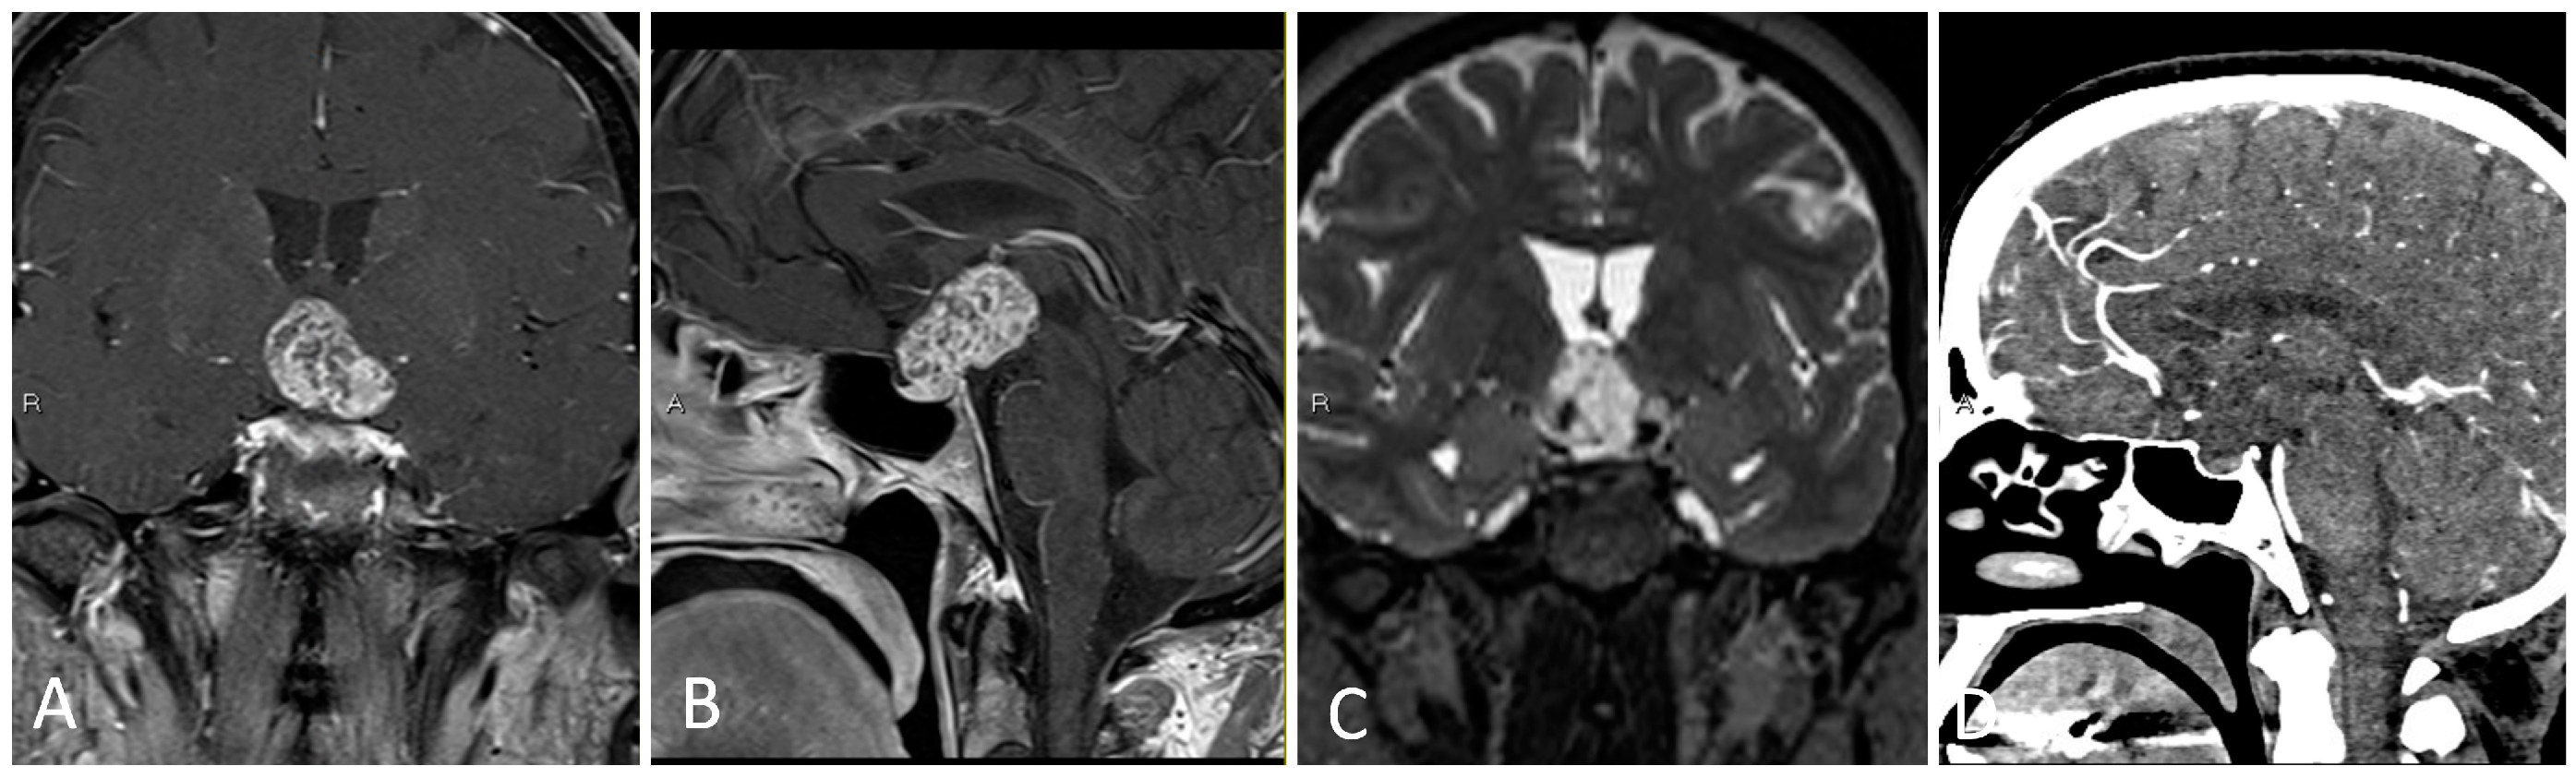

3.3.2. Illustrative Case

- Anterior and posterior ethmoidal arteries should be ligated and cut close to midline in order to avoid retraction of these vessels into the orbit.

- The inlay dural substitute should be oversized as part of the multi-layered closure.

- Reconstruction with a nasoseptal flap should take into account sites of involved disease, which cannot be used in the flap.